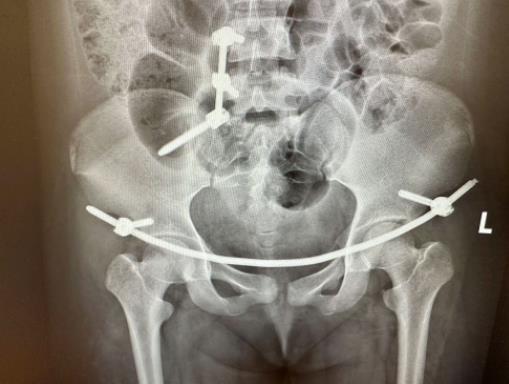

骨科负责人李书振主任医师带领科室团队为患者进行了详细检查,结果显示患者右侧骶骨Ⅰ区发生骨折,合并右侧骶髂关节及耻骨联合向上移位,被诊断为Tile C1型骨盆骨折,属于极其不稳定类型的骨折。

▲术前CT